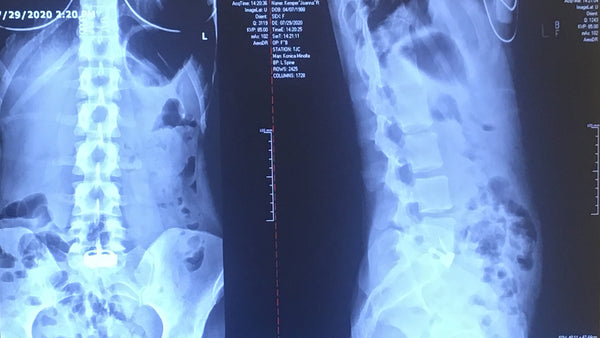

In 2020 the second MRI report confirmed: “Collapse of the L5-S1 disk space and retrolisthesis of L5 on S1 of about 3 to 4 mm. There is severe foraminal stenosis bilaterally because of the collapse. There are also modic type 1 endplate changes. At L4-L5, there is mild disk degeneration with an annular tear that appears stable compared to her previous MRI scan from three years ago.” Due to COVID, it was still a month of waiting before I could see a surgeon after hearing this news.

I had spine surgery on July 22, 2020, specifically an anterior lumbar interbody fusion (ALIF) at L5-S1. It is the best thing I did in 2020, that, and getting moral support kittens. My quality of life has improved exponentially, and though my struggle with pain is still very much real, I am privileged to share that this is my struggle. My pain has returned to the realm of manageable. Not everyone is as lucky. I am surrounded by the ongoing struggles of the people nearest and dearest to me. I know I am incredibly fortunate to be on the sunny side again, even if it’s still cloudy sometimes.